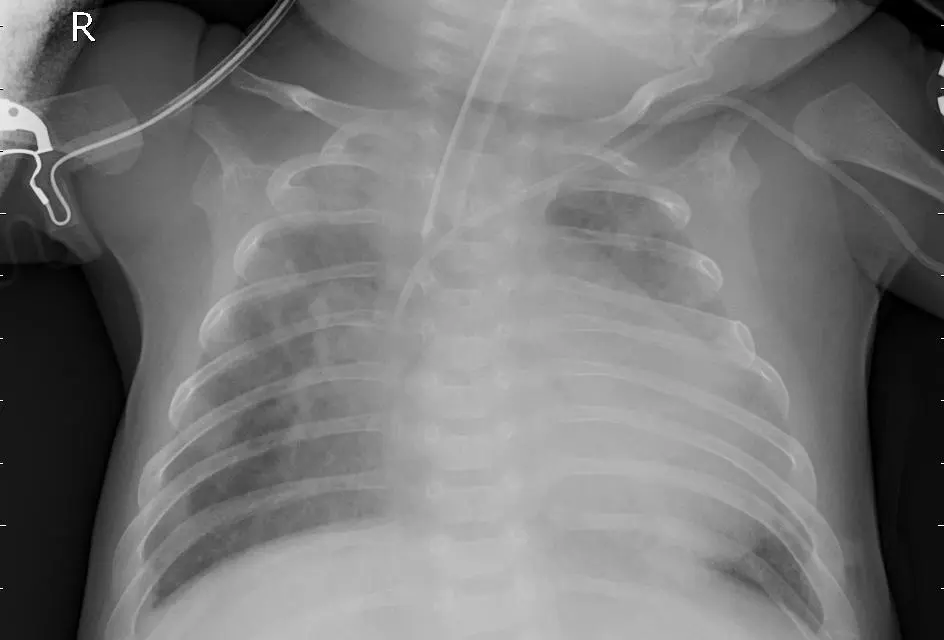

نموذج ذكاء اصطناعي باستخدام تقنيات Deep Learning لتحليل صور الأشعة الصدرية (Chest X-Ray) واكتشاف الإصابة بالالتهاب الرئوي (Pneumonia). المشروع يعتمد على شبكة CNN مدربة لتحليل الصور الطبية بدقة، مع توفير واجهة ويب بسيطة باستخدام Flask لرفع صورة الأشعة والحصول على النتيجة مباشرة. ما ستحصل عليه: * كود المشروع كامل بلغة Python * نموذج الذكاء الاصطناعي المدرب * تطبيق Flask لتحليل الصور * شرح طريقة تشغيل المشروع